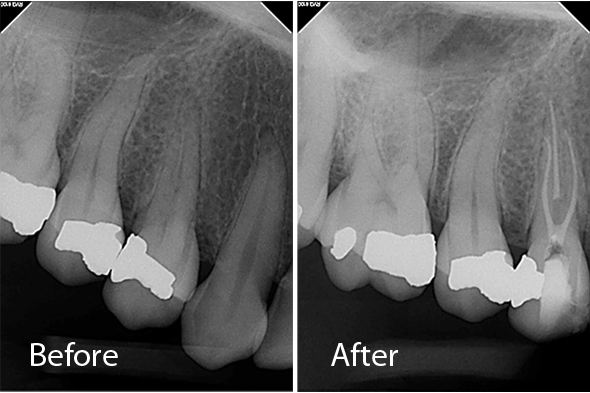

These X-ray images demonstrate the quality and precision of Dr. Portugeys' endodontic procedures. Click any image to view it larger.

Root Canal Molar